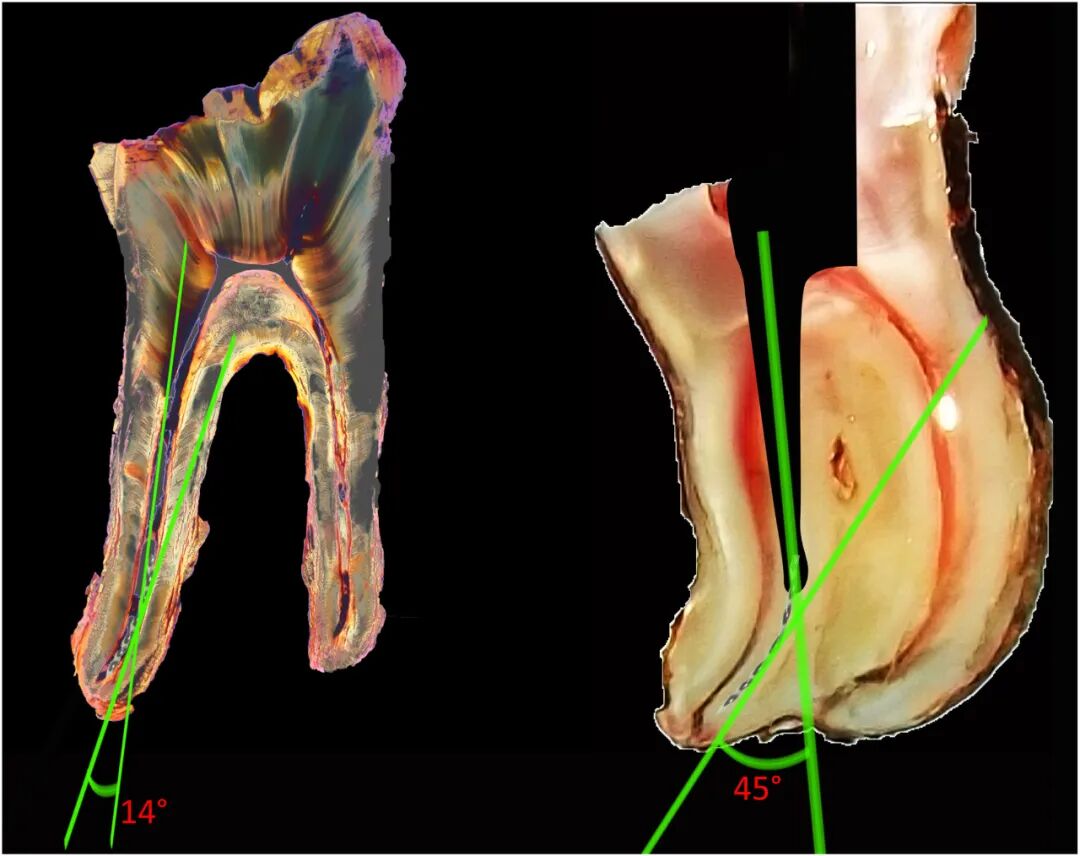

采用根管弯曲度的标准化测量方案,该法将根尖孔与分离器械断端作一连线,它与根管长轴的夹角为测量角(图1),然后在手术过程中进行临床确认。当该角度<15°时,为直根管的,其他情况则为弯曲的根管。根据根管的弯曲度,临床方案略有改变,如以下所述。

图1. 根管弯曲度的计算:从根尖孔到器械断端作一直线,测量它与根管长轴之间的夹角。当角度小于15°时,定义为直根管(左图),其他情况定义为弯曲根管(右图)。